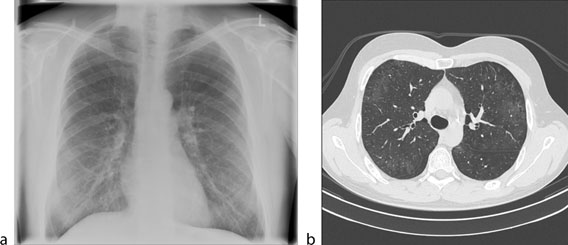

A Chest X Ray With A Miliary Pattern And A Tree In Bud Sign Download Scientific Diagram

A 70-year-old woman with transitional cell carcinoma and no pulmonary symptoms. There is a cluster of small tree-in-bud TIB opacities arrowheads in the left upper lobe. Usually somewhat nodular in appearance the tree-in-bud pattern is generally most pronounced in the lung periphery and associated with abnormalities of the larger airways.

A young male patient who had a history of fever cough and respiratory distress presented in the emergency department. Tree in bud opacification refers to a sign on chest CT where small centrilobular nodules and corresponding small branches simulate the appearance of the end of a branch belonging to a tree that is in bud. Tree-in-bud refers to a pattern seen on thin-section chest CT in which centrilobular bronchial dilatation and filling by mucus pus or fluid resembles a budding tree.

The tree-in-bud-pattern of images on thin-section lung CT is defined by centrilobular branching structures that resemble a budding tree. Not only are these patterns difficult to detect but micro-nodules and other normal and abnormal structures have strong shape and appearance similarities with existing structures in the lungs. What does opacity mean on chest xray.